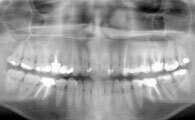

Une radio panoramique dentaire est un cliché de l'ensemble de la denture et des articulations temporo-mandibulaires.